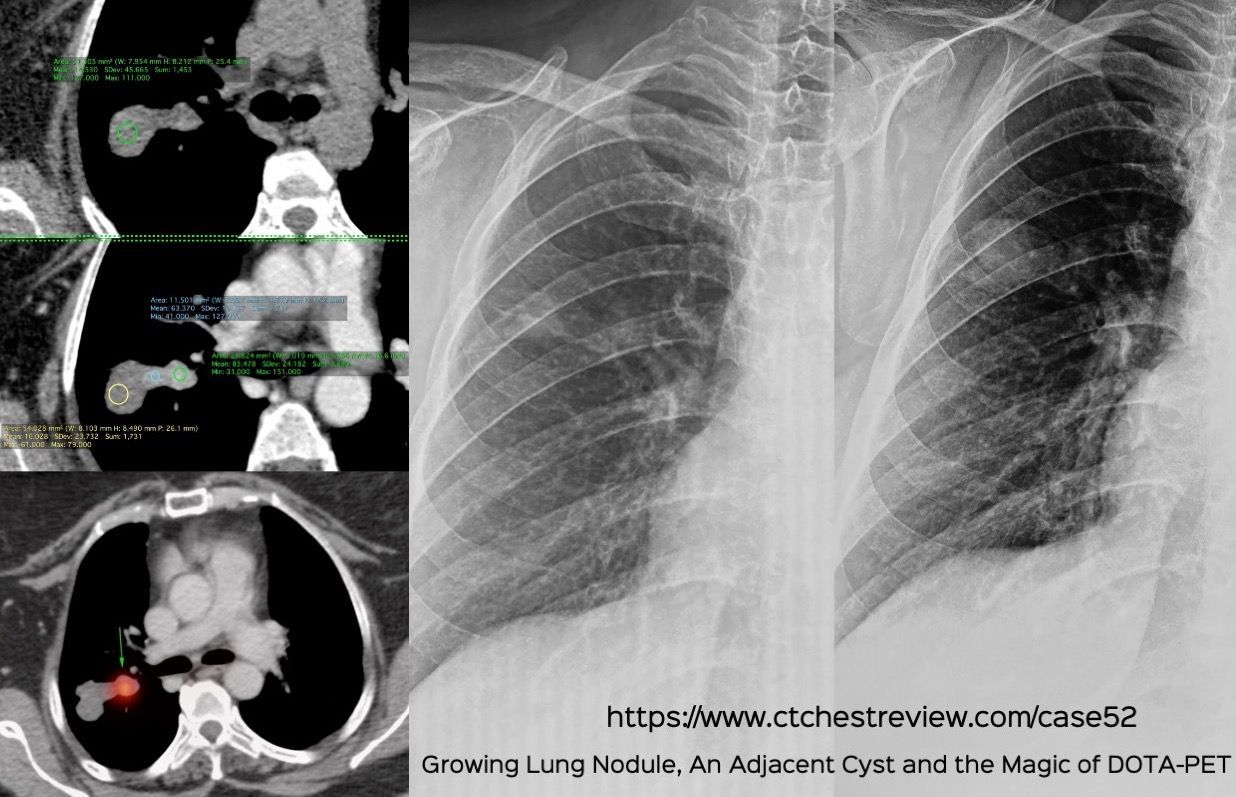

Case 52: A Growing Lung Nodule, An Adjacent Cyst and the Magic of DOTA-PET Members Public

A Growing Lung Nodule, An Adjacent Cyst and the Magic of DOTA-PET

Lung Nodule